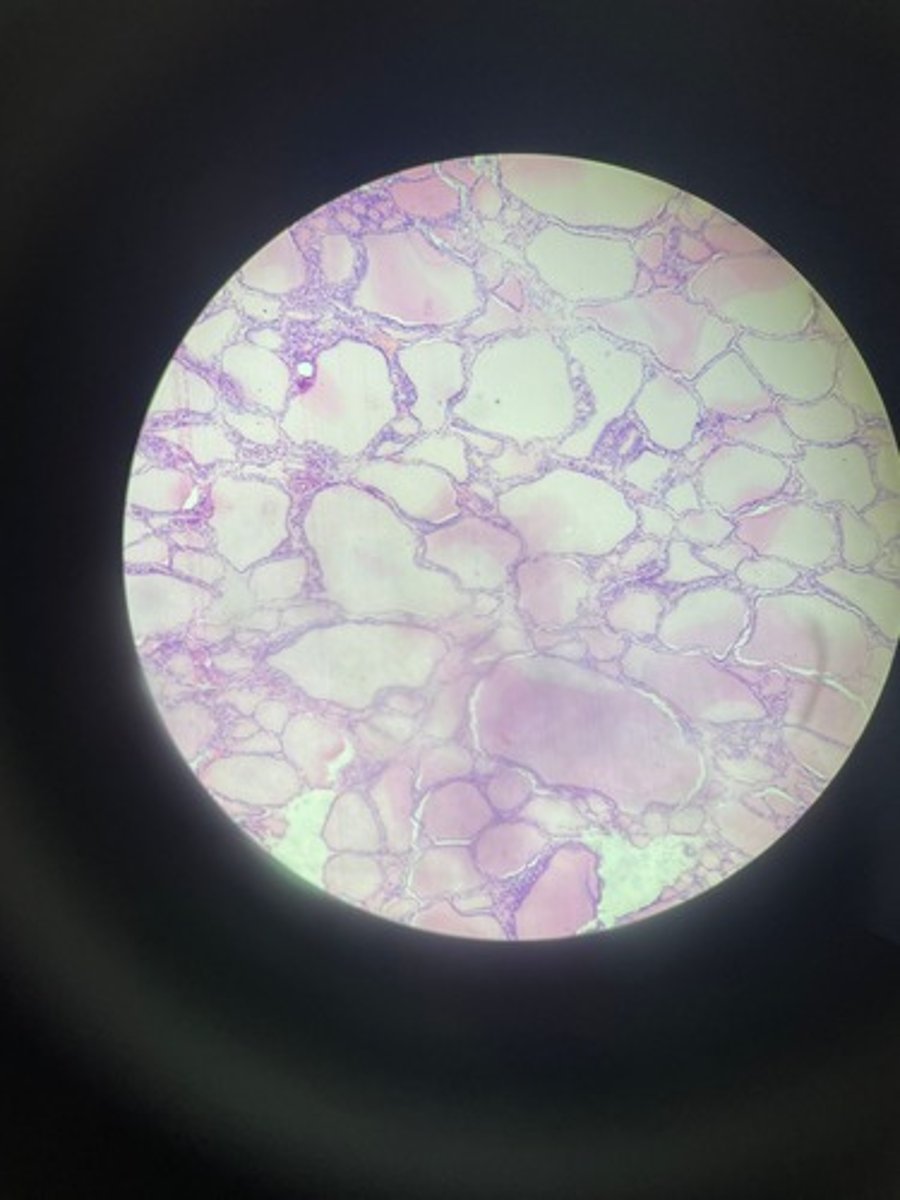

Thyroid gland HE

Thyroid gland HE

Thyroid gland HE

Thyroid HE

Thyroid HE